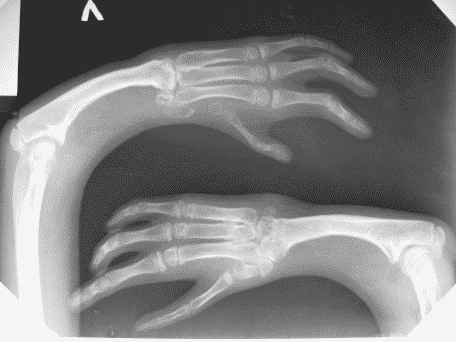

Мальчику 12 лет, страдает аномалией развития верхних конечностей.

Ребенок был оперирован несколько раз в другом городе. На сегодняшний день у пациента выражена деформация левого предплечья и оба предплечья короткие. У пациента и родителей есть желание удлинить предплечья.

Функция кистей нарушена, сгибание в локтевых суставах в полном объеме.

Движение в локтевых суставах в полном объеме (сгибание- разгибание)В лучезапястных суставах движения минимальны в диапазоне 5/0/5градусов.

Кликните для загрузки файла IMG_1585q2.bmp